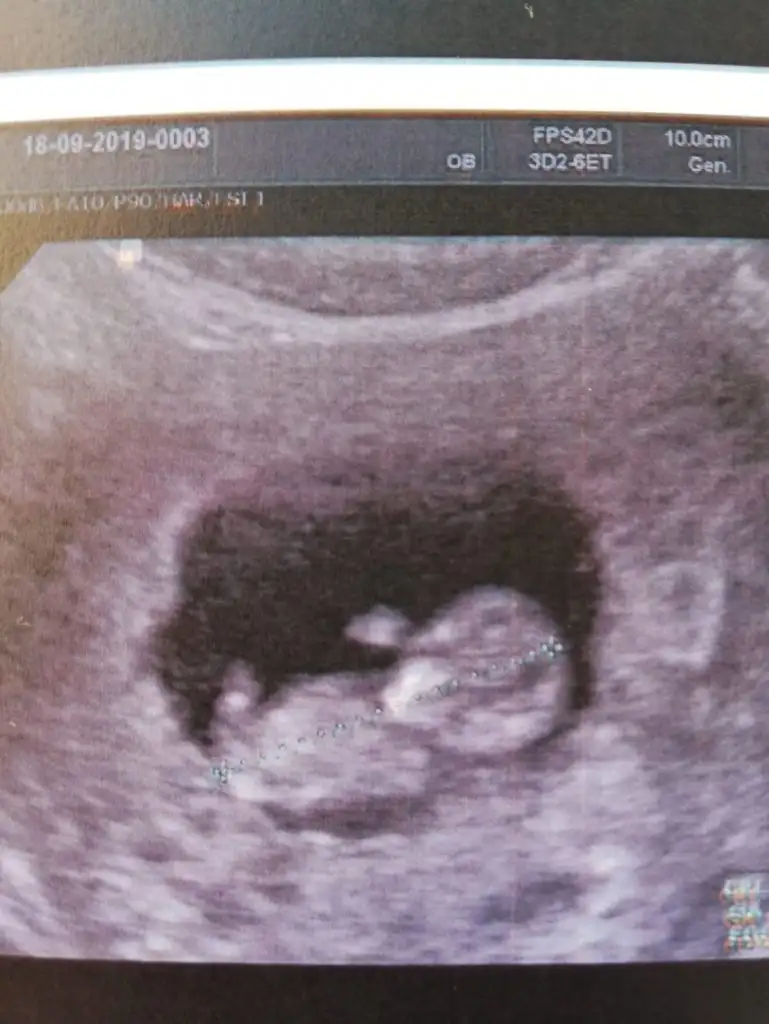

Kuzenimin bebişi 10 haftalık.. Cinsiyet tahmini yapar mısınız kızlar... Benimkini doğru bilmiştiniz

• IMG-20190918-WA0012.webp

IMG-20190918-WA0012.webp

13,3 KB · Görüntüleme: 58

• IMG-20190918-WA0013.webp

IMG-20190918-WA0013.webp

33,4 KB · Görüntüleme: 52

• IMG-20190918-WA0014.webp

IMG-20190918-WA0014.webp

33,1 KB · Görüntüleme: 59